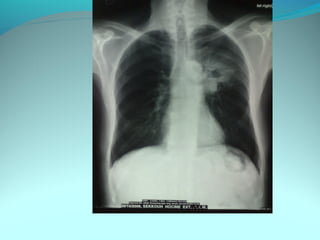

Opacité latéro_trachiale et hilaire droite grossierement arrondie de

6cm de diam dense et homogene

 la limite interne se confend avec le mediastin et la limite externe

nette convexe vers le mediastin

elle confond avec le mediastin évoquant une image mediastinale

Par ailleur on note:

Une surrélevation de la coupole diaph

Un coblement …..

DIAGNOSTIC:

Lymphome H ou NH

Volumineuse ADP tuberculeuse ou sarcoidosique